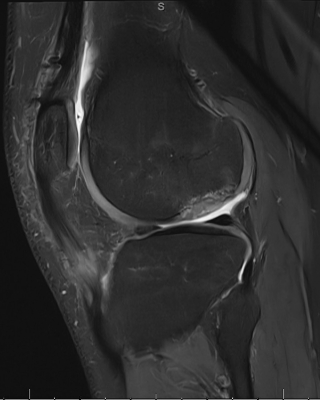

“We decided to try the live allograft first because, while we planned for two surgeries, we wondered if we could achieve something meaningful in a single-stage procedure under a single anesthesia event in a pediatric patient,” says Dr. Kannan. “Three months post-surgery, we obtained an MRI and noted the area we grafted healing beautifully — cartilage and underlying bone reconstituted, matching his femoral condyle contour perfectly. At three months, that’s remarkable.”